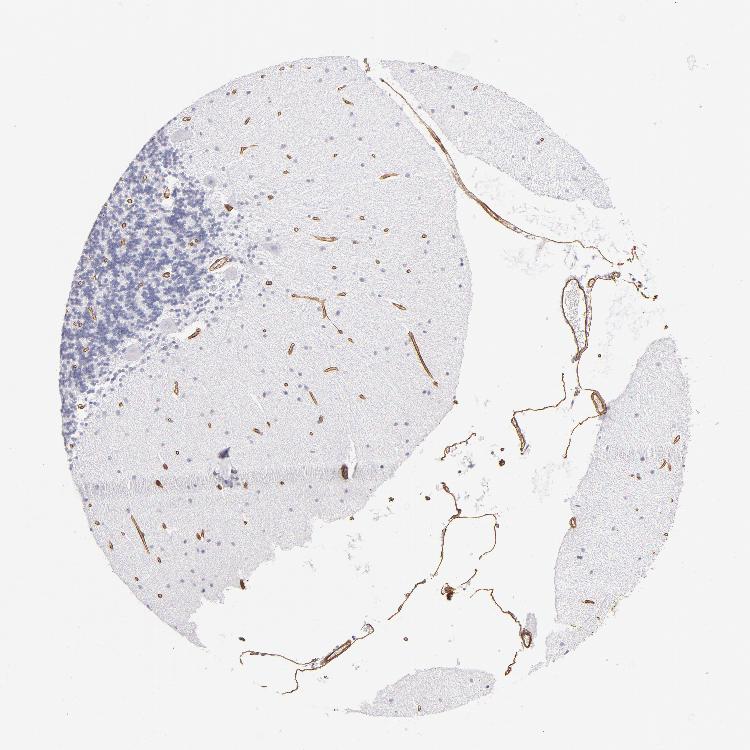

CEREBELLUM - Antibody stainingi

Antibody staining in the annotated cell types in the current human tissue is reported as not detected, low, medium, or high, based on conventional immunohistochemistry profiling in selected tissues. This score is based on the combination of the staining intensity and fraction of stained cells.

Each image is clickable and will lead to virtual microscopy that enables deeper exploration of all samples and also displays staining intensity scores, fraction scores and subcellular localization as well as patient and tissue information for each sample.

Antibody HPA001908Antibody HPA001909Antibody CAB004486Antibody CAB078163

Purkinje cells Not detectedNot detectedNot detectedNot detected

Cells in granular layer Not detectedNot detectedNot detectedNot detected

Cells in molecular layer LowNot detectedNot detectedNot detected